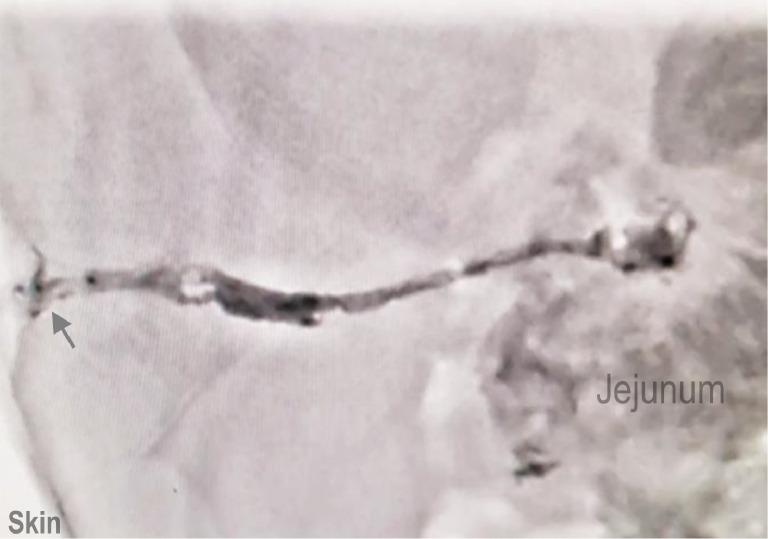

This case report highlights a minimally invasive approach to the management of enterocutaneous fistulas (ECFs), specifically jejunocutaneous fistulas (JCFs), using n-butyl cyanoacrylate (NBCA) glue. The patient, a 77-year-old female with Crohn's disease, presented with abdominal pain, fever, chills, and persistent discharge from the JCF site. Conventional treatment options for ECFs, ranging from conservative management to surgical intervention, are often associated with morbidity and prolonged recovery periods. This case demonstrates the successful closure of a JCF using NBCA glue injection, resulting in complete symptom resolution and sustained fistula closure at 18 months follow-up. The application of NBCA glue represents a promising alternative to traditional approaches, offering reduced procedural risks and shorter recovery times. This report highlights the role of minimally invasive techniques in the management of ECFs and highlights the need for further studies to establish standardized protocols and expand the clinical use of this approach.